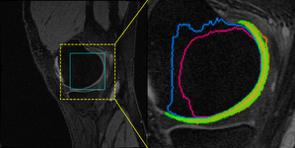

Accurate magnetic resonance imaging (MRI) segmentation is crucial for clinical decision-making, but remains labor-intensive when performed manually. Convolutional neural network (CNN)-based methods can be accurate and efficient, but often generalize poorly to MRI's variable contrast, intensity inhomogeneity, and protocols. Although the transformer-based Segment Anything Model (SAM) has demonstrated remarkable generalizability in natural images, existing adaptations often treat MRI as another imaging modality, overlooking these modality-specific challenges. We present SAMRI, an MRI-specialized SAM trained and validated on 1.1 million labeled MR slices spanning whole-body organs and pathologies. We demonstrate that SAM can be effectively adapted to MRI by simply fine-tuning its mask decoder using a two-stage strategy, reducing training time by 94% and trainable parameters by 96% versus full-model retraining. Across diverse MRI segmentation tasks, SAMRI achieves a mean Dice of 0.87, delivering state-of-the-art accuracy across anatomical regions and robust generalization on unseen structures, particularly small and clinically important structures.